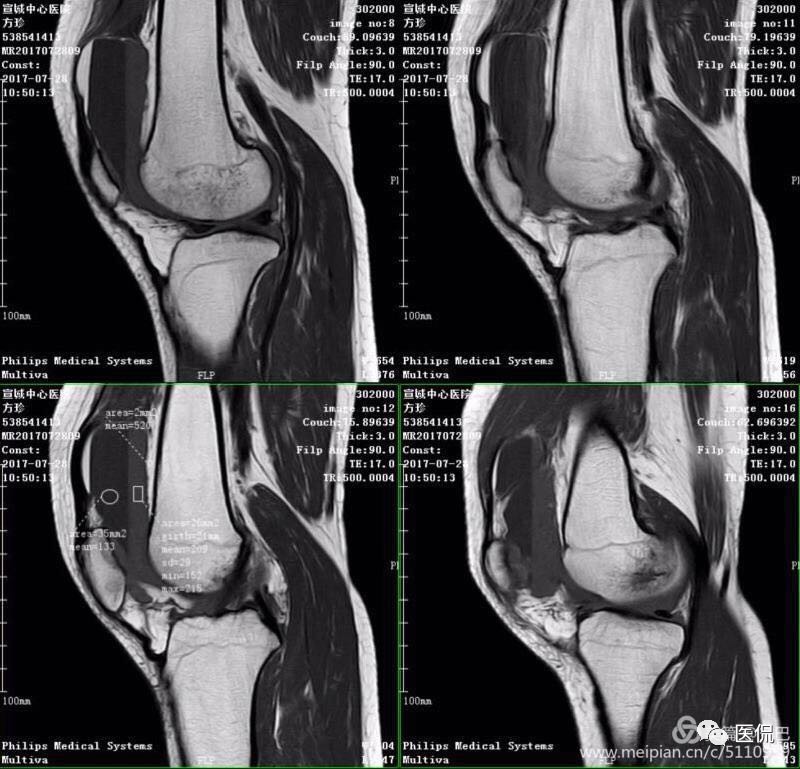

MR表现

1、单液-液平面:上层呈短T1、长T2信号、T2压脂像低信号、Pd像呈高信号;下层呈中等T1、T2信号、T2压脂像和Pd像呈较高信号。

2、双夜-液平面:上层呈短T1、长T2高信号、T2压脂像低信号、Pd像呈高信号;中层呈长T1、长T2信号、T2压脂像和Pd像呈较高信号;下层呈中等T1、T2信号、T2压脂像和Pd像呈较高信号。

3、多液-液平面:最上层呈无信号区;上层呈短T1、长T2高信号、T2压脂像低信号、Pd像呈高信号;中层呈长T1、长T2信号、T2压脂像和Pd像呈较高信号;下层呈中等T1、T2信号、T2压脂像和Pd像呈较高信号。